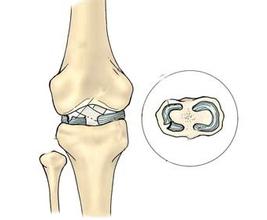

• [分型] 膝关节创伤性滑膜炎

导读: 膝关节是全身关节中滑膜面积较大的关节,滑膜反应也较明显。膝关节创伤性滑膜炎是指膝关节囊纤维的内衬滑膜在外伤后引起的滑膜非感染性炎症反应。临床上分为急性创伤性炎症和慢性劳损性炎症两种。若确诊为本病应积极